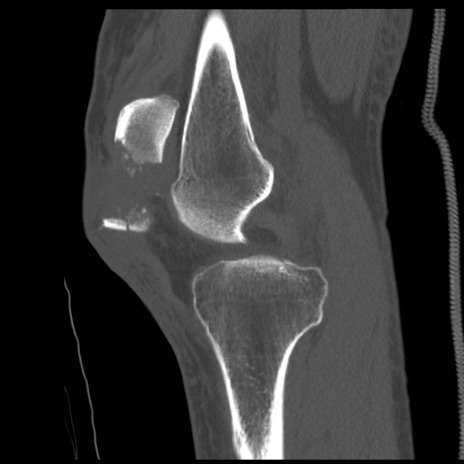

症例28 右膝関節CT(矢状断像)

右膝関節CT